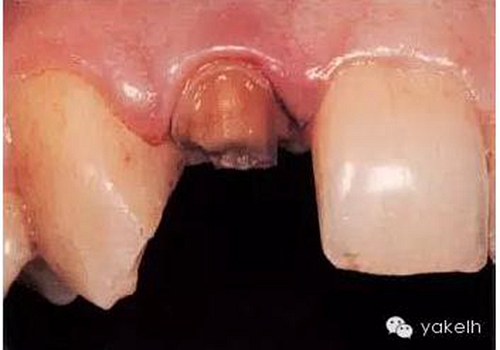

¤¤最終,患者同意12根管再治療后樁核冠修復(fù)。臨床上,應(yīng)在拆除現(xiàn)有修復(fù)體、評(píng)估冠部剩余牙體量后,方能確定最終治療方案(圖6.3.2)。

圖6.3.2 拆除12現(xiàn)有修復(fù)體后剩余的牙體組織。